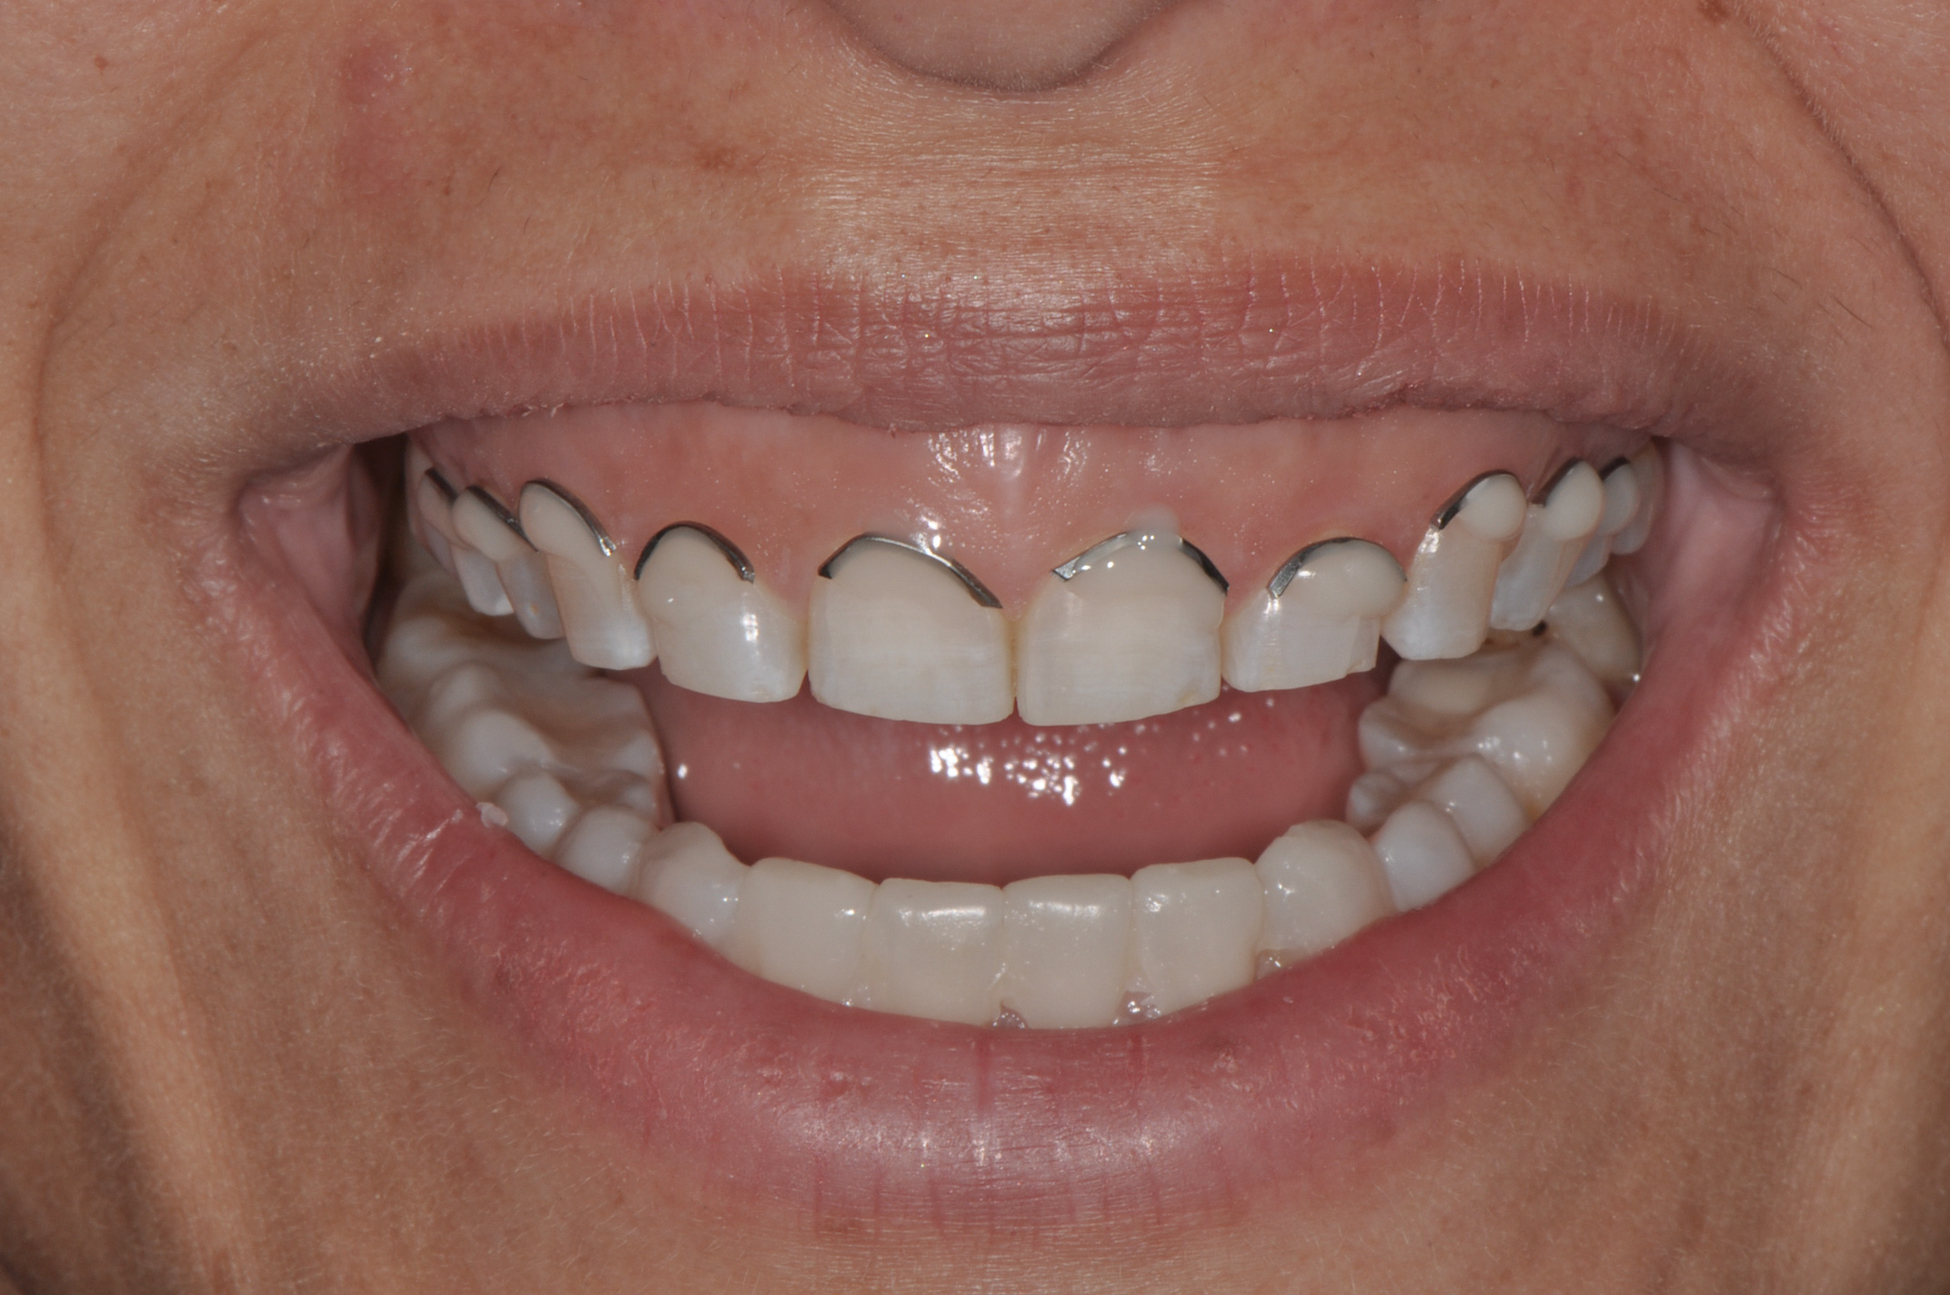

Fig 2. Resolution of gummy smile after treatment in patient shown in Fig 1.

Figure 2